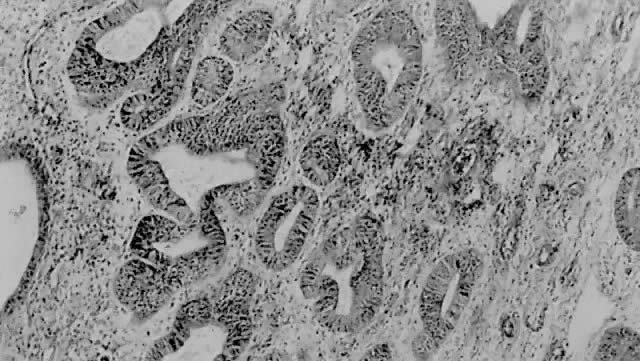

Fig. 5. ( A) Long papillary stalks lined by endometrioid-type cells are characteristic of the villoglandular or papillary variant of endometrial adenocarcinoma. ( B) The papillae are lined by stratified cells demonstrating mild nuclear atypia. Cellular budding and high-grade nuclear features are absent, aiding in distinguishing this lesion from serous carcinoma.